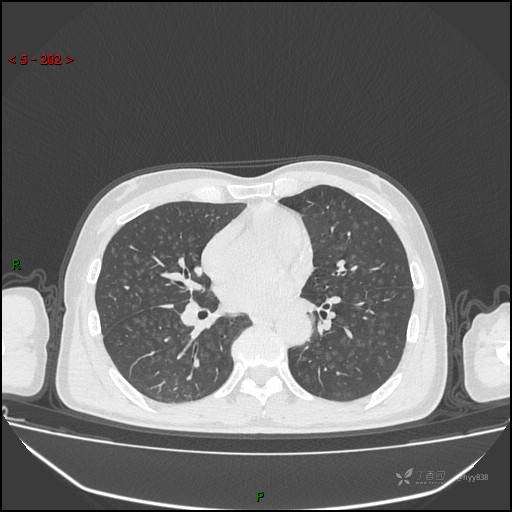

性别:男

年龄:55岁

简要病史:渐进性呼吸困难。

实验室检查:血象正常。

临床诊断:呼吸困难待查

胸部CT平扫

电焊工尘肺 (2)